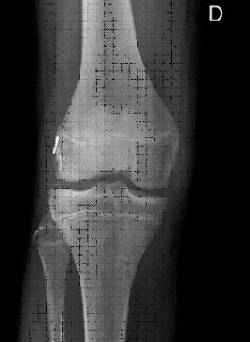

Els tractaments convencionals descrits per a la reparació del lligament creuat anterior poden provocar efectes iatrogènics sobre el cartílag de creixement.

El factor determinant en la possibilitat de l’aparició d’aquests efectes adversos no és l’edat cronològica del pacient, sinó el seu estadi maduratiu (estadis de Tanner <II determinats per l’aparició de caràcters sexuals secundaris).

També estan involucrats en la possibilitat de lesionar el cartílag de creixement el tipus d’empelt utilitzat (amb pastilles òssies), una excessiva tensió d’aquest a l’hora d’implantar-lo i el diàmetre de les tunelitzacions emprades.